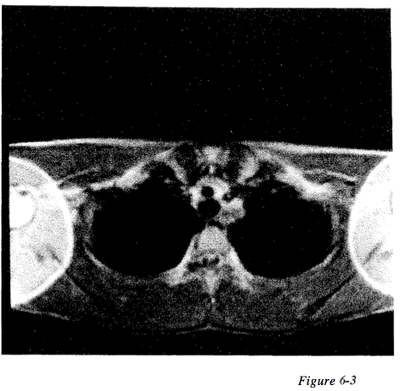

Question 58

Question

Figure 6-3 displays an example of what type of artifact

Answer

• Ringing

• Phase wrap

• Chemical shift

• Cross talk